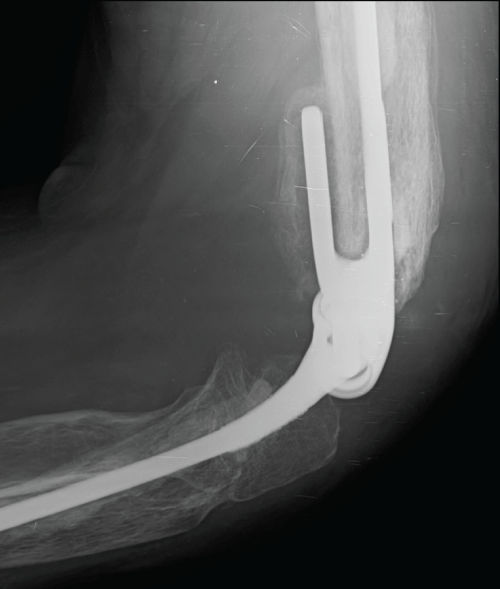

In order to exclude possible infection, we monitorized the C-reactive protein levels, which decreased gradually. Two months later, the X-ray and the Computed Tomography showed signals of malunion (Figure 3) and the external fixator was removed. In the postoperative period we noticed an important elbow instability and reduced mobility. We considered multiple treatment options and concluded that internal fixation would not be possible given the absence of adequate articular surfaces. In this sense, we decided to perform a total elbow arthroplasty three months after the accident. By a posterior approach, the triceps was externally reflected, the distal humeral extremity was regularized, the bone sequestra were removed and the ulna was prepared. A linked arthroplasty was applied - Coonrad-Morrey total elbow arthroplasty. The extensor apparatus was inserted directly over the prosthesis (Figure 4). Ulnar nerve transposition was not necessary.

In the postoperative period, we verified adequate healing and the X-ray revealed correct prosthesis implantation (Figure 5). Two weeks later, the patient began rehabilitation with passive elbow motion that gradually progressed to active motion. Six weeks after surgery, the patient was capable of feeding himself and began strength exercises. We verified a progressive increase in strength and in range of motion. Six months after arthroplasty, the patient resumed his laboral activity and presented with no pain or sensory alterations. Furthermore, he presented a range of motion of 0-135°, with a light supination deficit and a moderate muscular strength decrease.